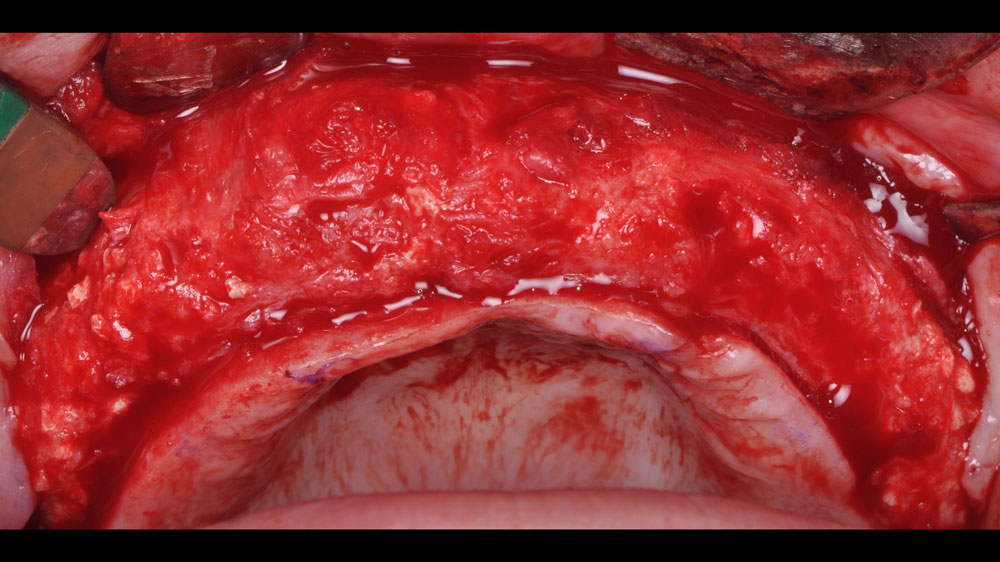

Horizontal and vertical ridge augmentation was performed using a full-thickness maxillary flap with two distal vertical releasing incisions. Extensive buccal periosteal release and cortical perforations were carried out. A composite graft of large-particle vallos® allograft (demineralized cortical granules) and large-particle Geistlich Bio-Oss® xenograft, combined with rhPDGF-BB, a component of GEM 21S®, was placed and stabilized under a high-density PTFE membrane, which was secured with four horizontal mattress and multiple simple interrupted 4-0 PTFE sutures.

Horizontal (5–7 mm) and vertical (3–4 mm) ridge augmentation were successfully obtained, with stablewound management achieved through precise suturing techniques. The osteoinductive properties of the large vallos®, demineralized granules combined with rhPDGF-BB, a component of GEM21S® promoted high-quality bone regeneration, whereas the large Geistlich Bio‑Oss®, xenograft particles contributed to volume preservation by moderating resorption. As a result, four 4.3 mm implants were placed with high primary stability, each exceeding 35 N·cm of insertion torque, providing a strong foundation for a predictable esthetic and functional restoration.